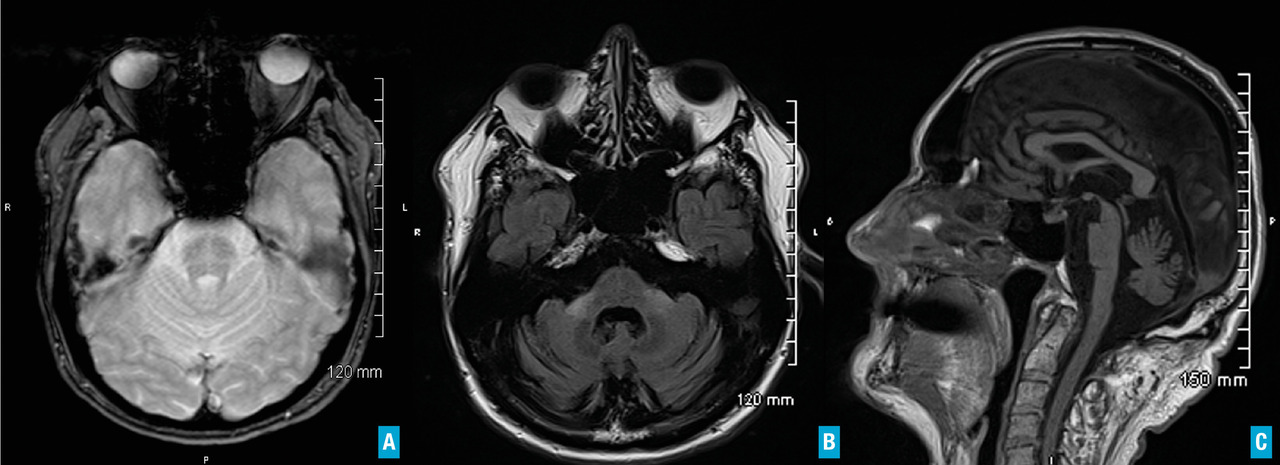

L’imagerie cérébrale morphologique et fonctionnelle (fig. 2-7) occupe une place prépondérante dans la recherche d’arguments en faveur d’une pathologie neurométabolique (maladie de Wilson chez les sujets jeunes), de lésions vasculaires ou d’une hydrocéphalie à pression normale. L’IRM cérébrale permet également de mettre en évidence des anomalies évocatrices de certains syndromes parkinsoniens dégénératifs.